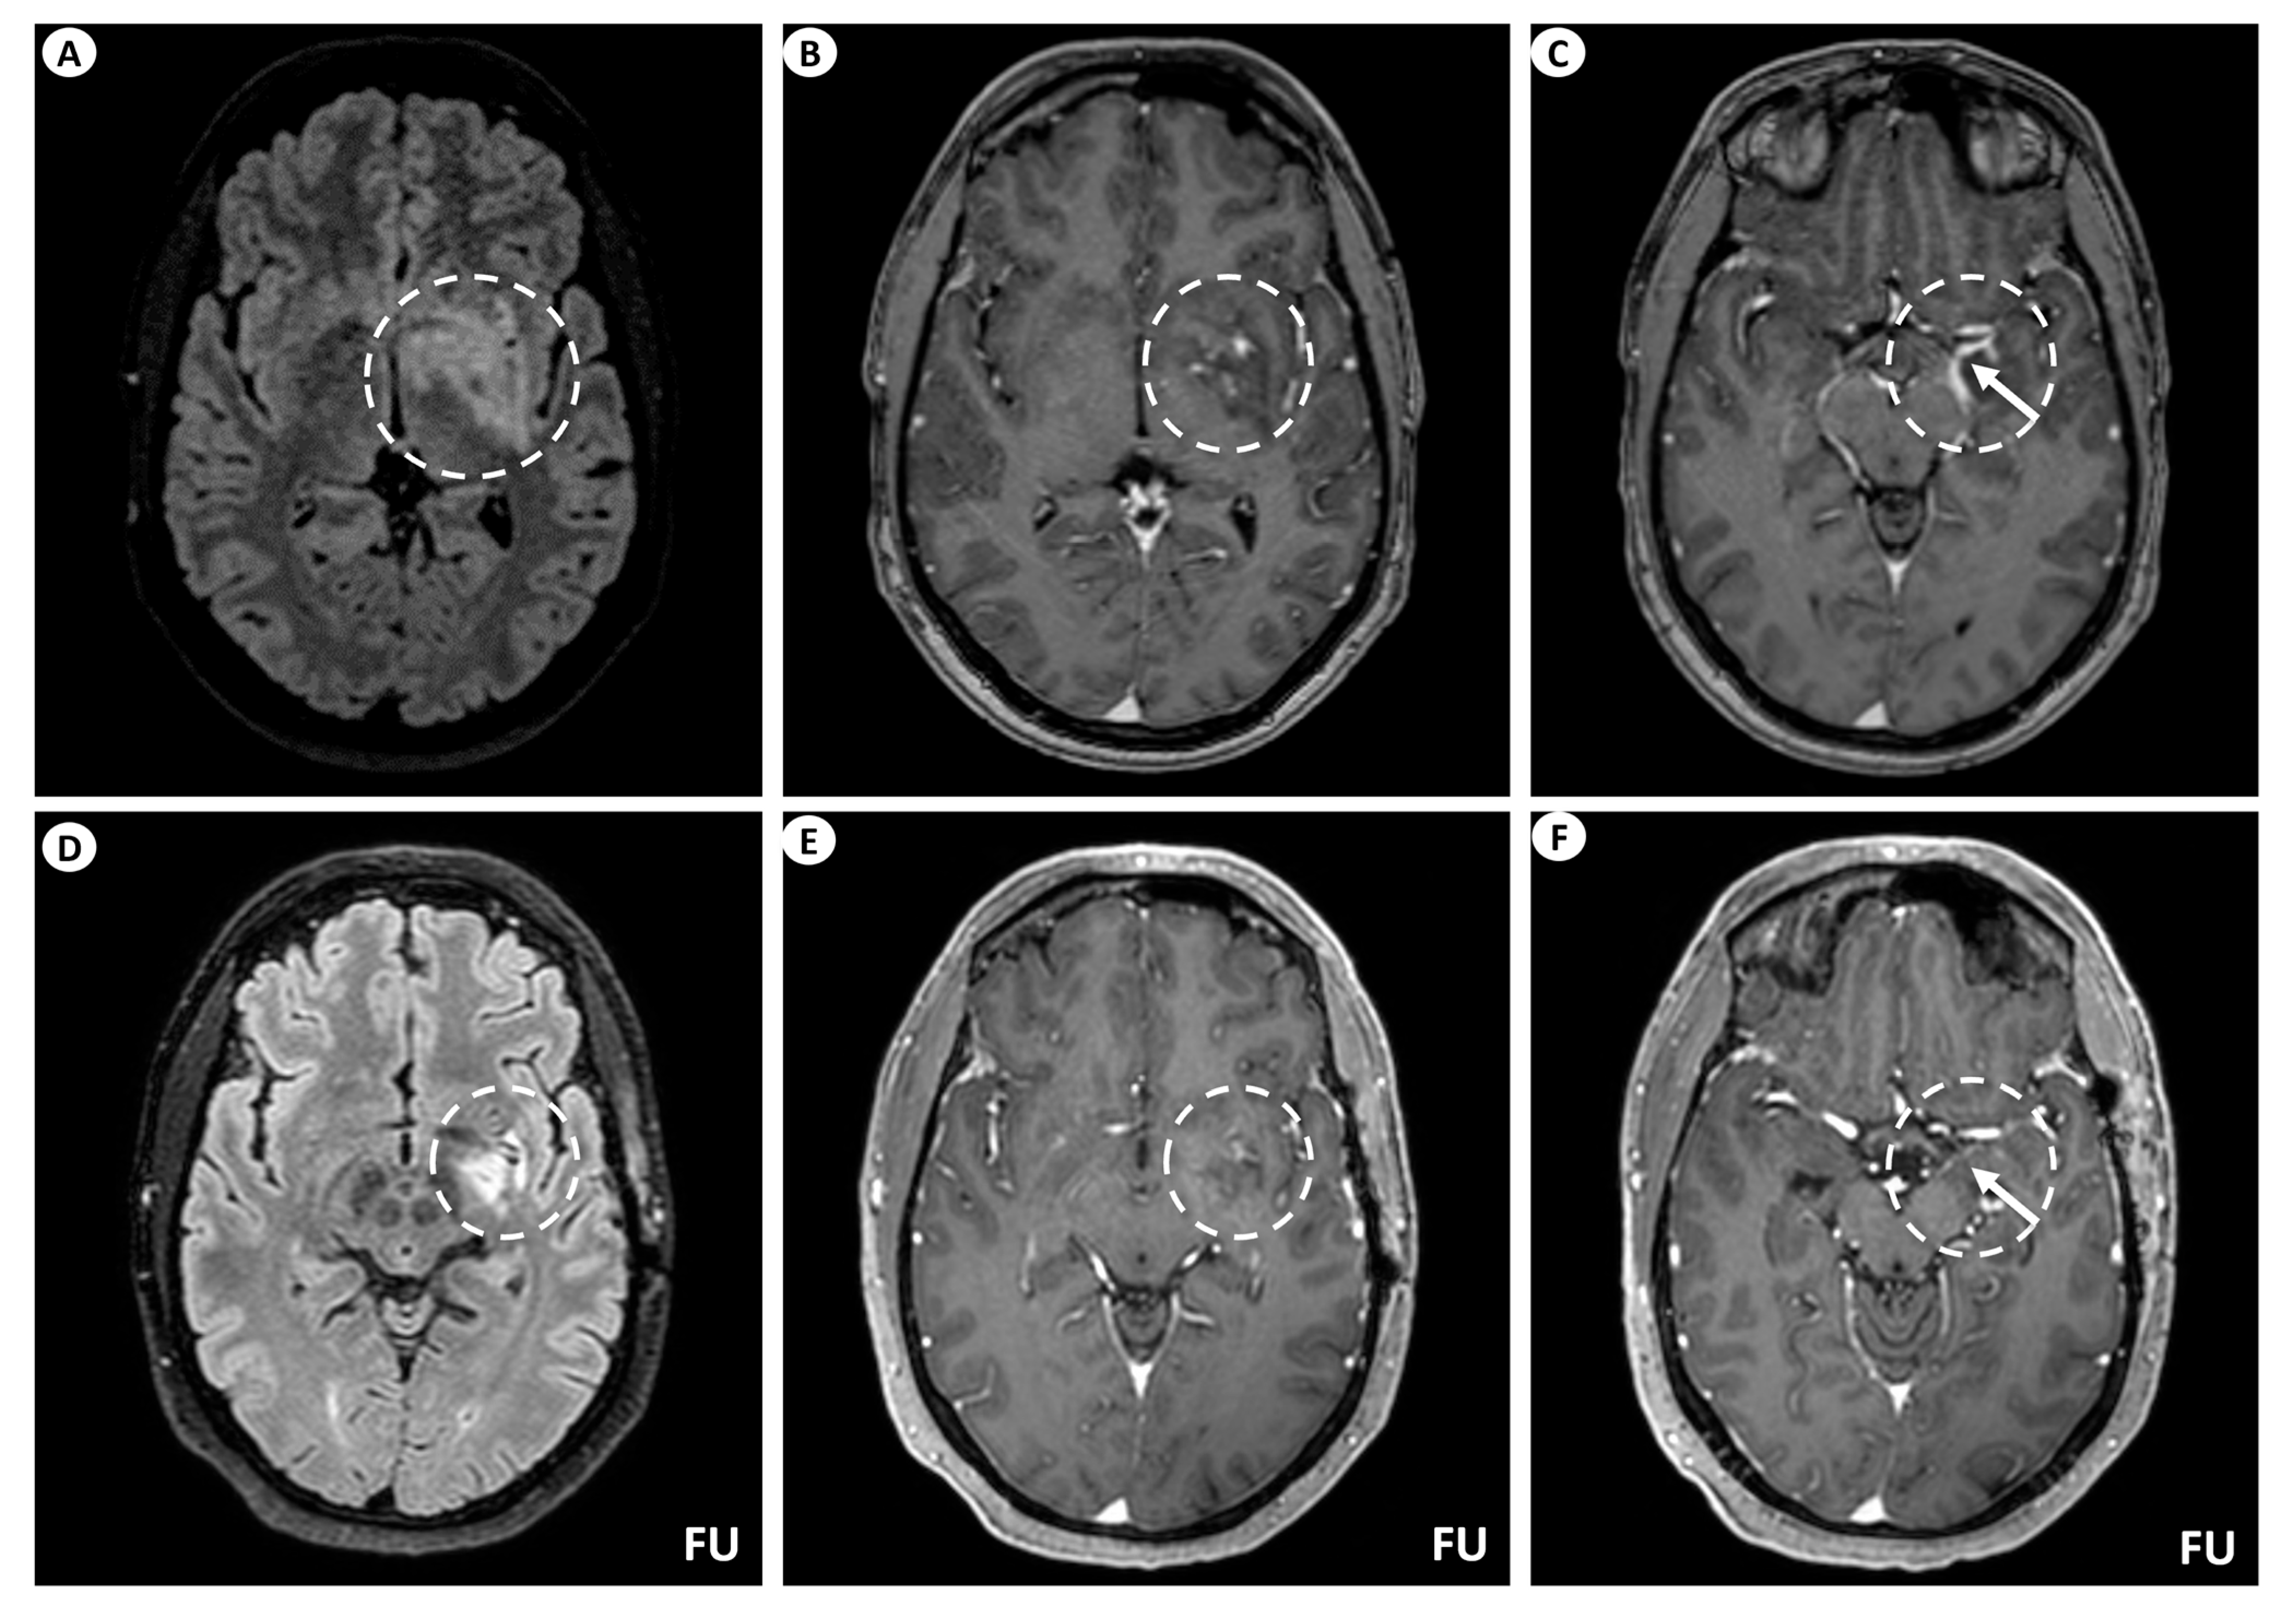

A 44-year-old man presented with persistent, left-sided, daily headache episodes of tightening quality and medium severity (visual analog scale score 6/10) over the past 15 days. No prior history of headaches was reported, and his past medical history was insignificant except for smoking (40 pack-years). Neurological examination was completely normal. Magnetic resonance imaging (MRI) of the brain revealed T2/fluid-attenuated inversion recovery (FLAIR) signal hyperintensity within the basal ganglia (putamen, globus pallidus), internal capsule, medial temporal lobe, hypothalamus, and midbrain on the left. Linear perivascular radial gadolinium enhancement was also observed, extending along the perivascular spaces in these areas, as well as leptomeningeal contrast enhancement along the surface of the uncus (Figure 1). The patient did not have a lumbar puncture but instead underwent a brain biopsy, which was inconclusive, and received a short course of oral steroids following the biopsy. He was subsequently lost to follow-up but was eventually readmitted for further investigations. At that time, he underwent a lumbar puncture, which showed no pleocytosis. Cerebrospinal fluid (CSF) protein, glucose levels, and IgG index were within normal ranges, while oligoclonal bands were negative. However, it is important to note that the lumbar puncture was performed 6 months after symptom onset and following steroid treatment. A second brain MRI showed significant improvement, with remission of the hyperintensities and of the contrast enhancement (Figure 1), while an MRI of the spinal cord did not reveal any signs of myelopathy or other abnormal findings. CSF and serum testing for GFAP antibodies returned positive, while antibody testing for autoimmune and paraneoplastic encephalitis, including surface and intracellular antibodies, was negative. The patient underwent computerized tomography (CT) of the chest and abdomen, which was normal, as well as a positron-emission tomography (PET) scan, which was negative for malignancy. Subsequently, he received a five-day course of intravenous (IV) steroids without tapering and has remained asymptomatic since then.

Figure 1. Brain MRI of patient 1. (A) Axial T2-FLAIR (fluid-attenuated inversion recovery) images display signal hyperintensity centered within the basal ganglia (putamen, globus pallidus) and internal capsule on the left (dashed circle). (B) Axial T1-weighted images following intravenous gadolinium injection demonstrate punctate as well as linear contrast enhancement extending along the perivascular spaces (dashed circle), and (C) leptomeningeal contrast enhancement along the surface of the uncus (as indicated by the arrow within the dashed circle). Follow-up (FU) MRI examination in the same patient displays a noteworthy decrease in the extent of the signal hyperintensity within the left basal ganglia on axial T2-FLAIR images (dashed circle) (D). Similarly, axial T1-weighted images following intravenous gadolinium injection demonstrate partial subsidence of the perivascular contrast enhancement (dashed circle) (E), and complete resolution of the leptomeningeal enhancement (arrow within the dashed circle) (F).